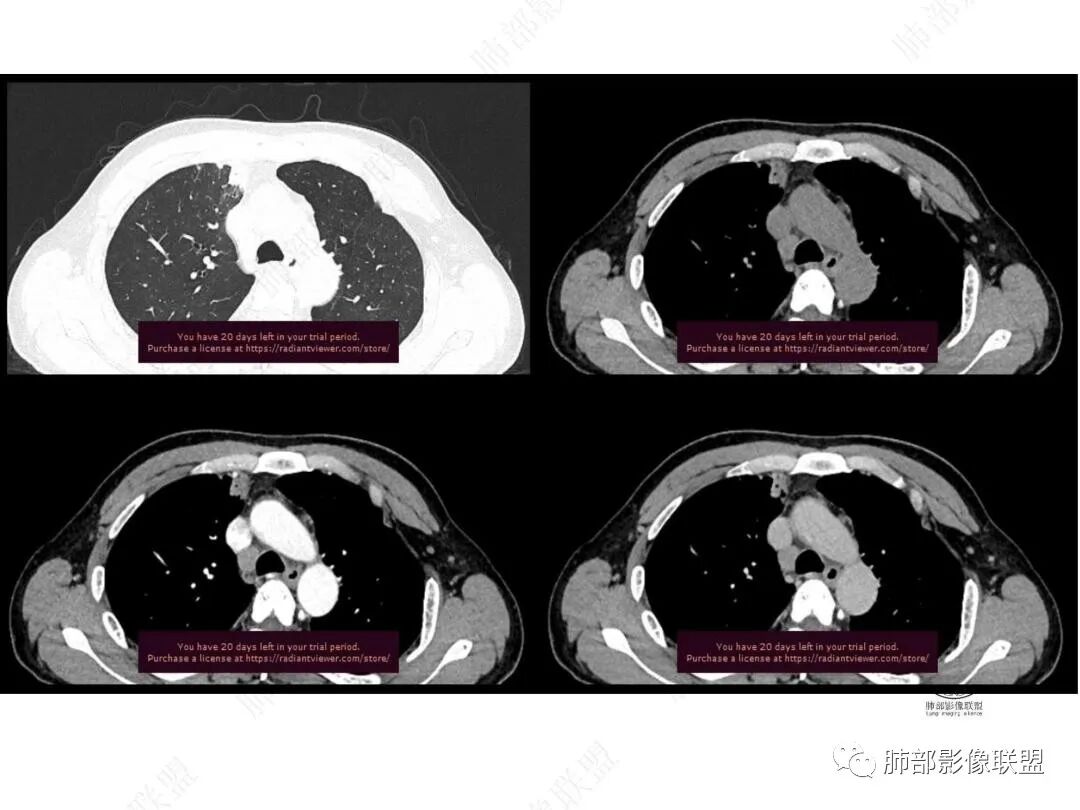

平扫图像

增强图像

CT值信息

右肺上叶前段纵隔旁见团块状影,边缘毛糙,部分直边,支气管进入,管壁增厚,密度均匀,明显强化。考虑炎性病变。纵隔胸膜似有栽桩,腺癌待排。

中年男性,慢性发热3月,白细胞总数及crp升高,右肺上叶实变影,边缘平直为主,似乎均匀强化,血管进入后截断,考虑血管相关性曲霉感染?

中年男性,前纵膈旁团块,边缘平直,周围可见模糊的磨玻璃影,相邻支气管壁增厚,部分支气管进入病灶后阻塞,增强病灶渐进性强化,肝右叶见边缘不清的低密度影,增强渐进性强化。结合实验室检查,总体考虑炎性病变,自免性炎症?血管炎?

男,49,低热3月。胸部CT:右肺上叶前段纵隔旁见团片影,部分边缘毛糙,部分平直、内收,邻近卫星灶、晕征,重建L征?支气管管壁增厚、进入后堵塞;纵隔可见肿大淋巴结;病灶密度较均匀,中度强化。肝脏片状低密度影,边缘模糊。考虑炎性病变,PC?TB?鉴别腺癌。

中年男性,反复低热3月伴近期乏力及右上腹隐痛,白细胞,中性粒及淀粉样蛋白A增高,PCT不高,IGA、IGg增高,类风湿因子增高,未提供IGg4水平,影像改变,左侧肋骨陈旧性骨折(2020年已存在)右上叶前段胸骨旁的胸膜下新发病灶,支气管进入后一段才堵塞,肺动脉进入,走行自然,未见破坏,明显均匀强化,气管及支气管壁有增厚,钙化,纵隔内淋巴结增大,均匀强化,无坏死,纵隔内脂肪混浊,局部强化,肝内低密度灶,延迟强化(肺内病灶,淋巴结、混浊脂肪,肝内病灶强化均一致,且均为延迟强化)。初步考虑:免疫相关性炎症,IGg4相关炎症可能大,依据:IGA、IGg增高(未提供IGg4,可能是故意隐藏了),类风湿因子增高,炎性指标增高,但PCT不高,细菌感染可能就变小,加上病变同时累及肺、纵隔淋巴结,纵隔内脂肪、肝。

1.中年男性,临床发热,症状较轻,中长病程,炎性指标轻度增高。

2.右肺上叶纵隔旁新发实性密度病灶,密度均匀,轻度强化,未见空洞、液化坏死及钙化,血管穿行自如,支气管进入后狭窄截止。灶周磨玻璃影边界不清,病灶未见明显分叶毛刺,平直、轻度收缩、周围偶见结节影,但未见树芽征。注意纵隔胸膜侵入或突入比较明确。纵隔淋巴结轻度增大。

3.右肺容易想到的病变有慢性炎症、IGg4相关、新生物(炎性肌纤维母细胞瘤、腺癌等)。但病灶侵入纵隔胸膜应当更符合恶性肿瘤。病程进展及强化等影像特点不支持继发性肺结核。